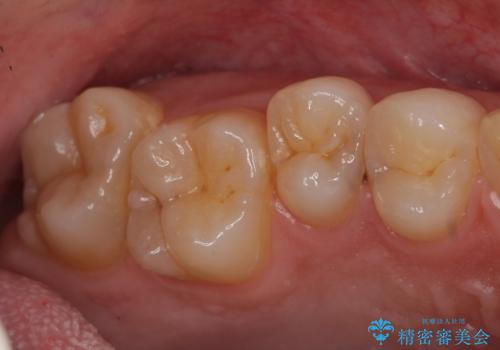

- 検査の結果左上の歯と歯の間に虫歯が発見された患者様です。

虫歯の除去後セラミックインレーでの修復処置をしていきます。

歯と歯の間は虫歯の好発部位とされています。

適合の良いインレーでの修復をすることで再発を防止します。